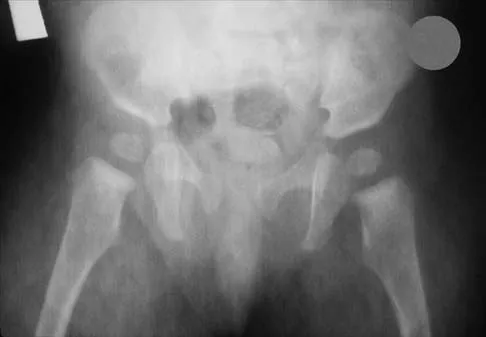

The mother of a 26-month-old boy reports that he has been unwilling to bear weight on his left lower extremity since he awoke this morning. She denies any history of trauma. He has a temperature of 99.4 degrees F (37.4 degrees C), and examination reveals that abduction of the left hip is limited to 30 degrees. Laboratory studies show a WBC of 11,000/mm3 and an erythrocyte sedimentation rate of 22 mm/h. A radiograph of the pelvis is shown in Figure 13. Management should consist of